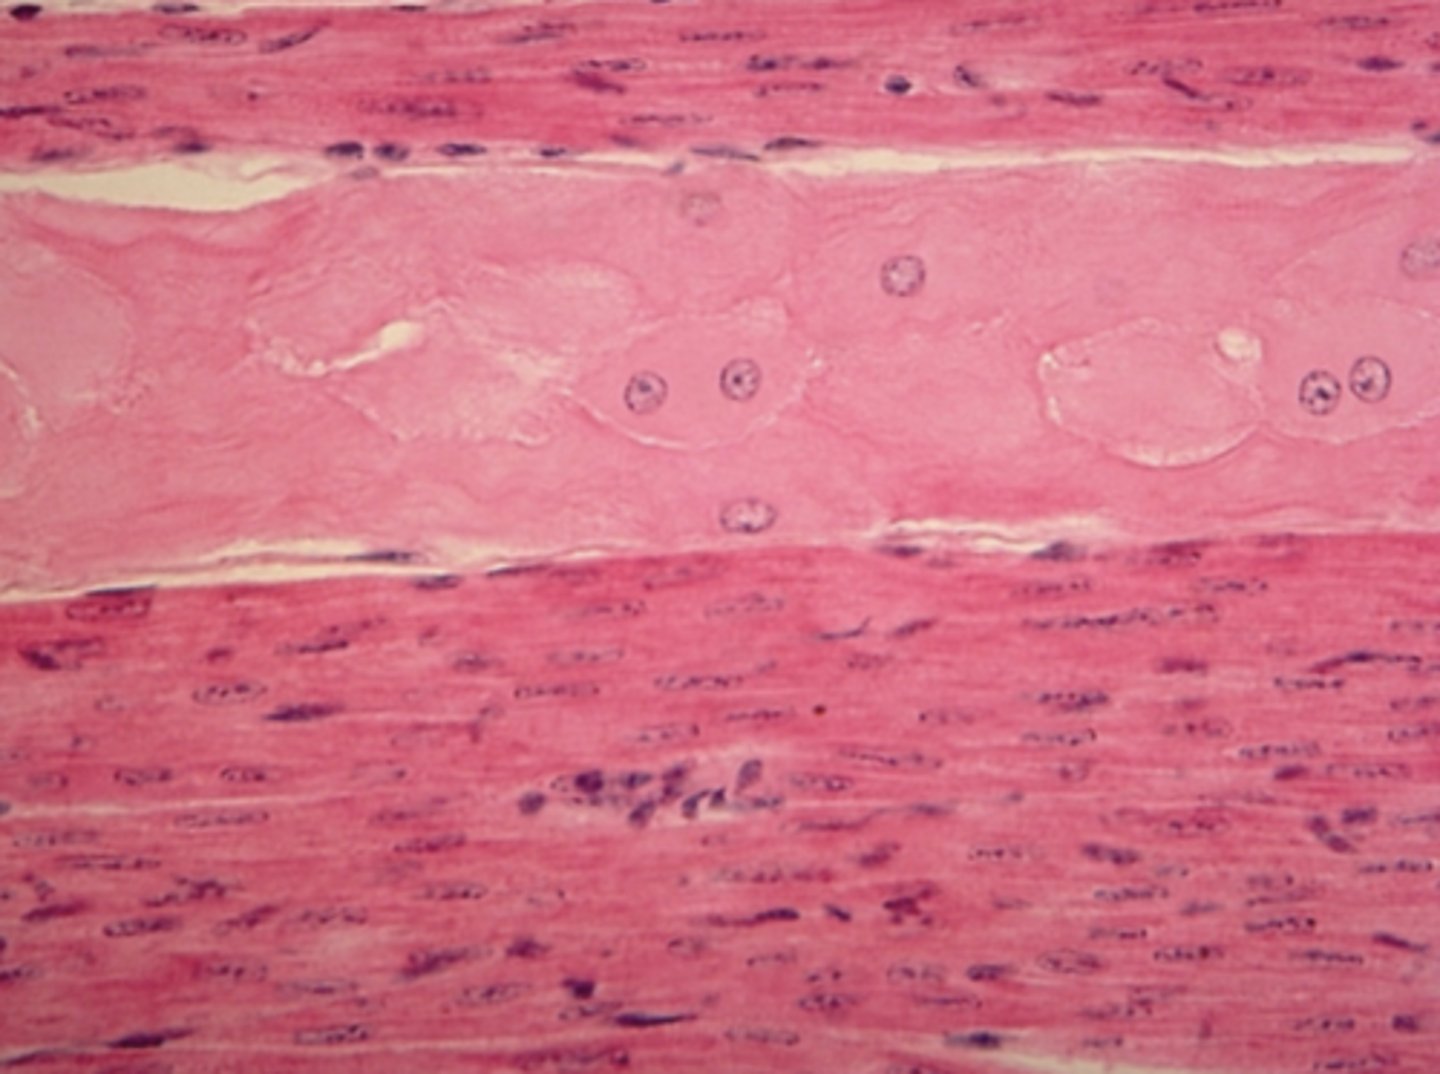

Muscle tissue

Which of the four major tissue types is presented in the following image of the heart:

Branched, striated cells with a central nucleus

Which is a feature of the tissue in the previous image of the heart (muscle tissue):

Tapered, non-striated cells with a central nucleusb. Branched, striated cells with a central nucleus

Branched, striated cells with a central nucleus

Long, striated cells with multiple peripheral nuclei

skeletal muscle

Which of the three muscle tissue types is presented in the following image:

cardiac

Which of the three muscle tissue types is presented in the following image: